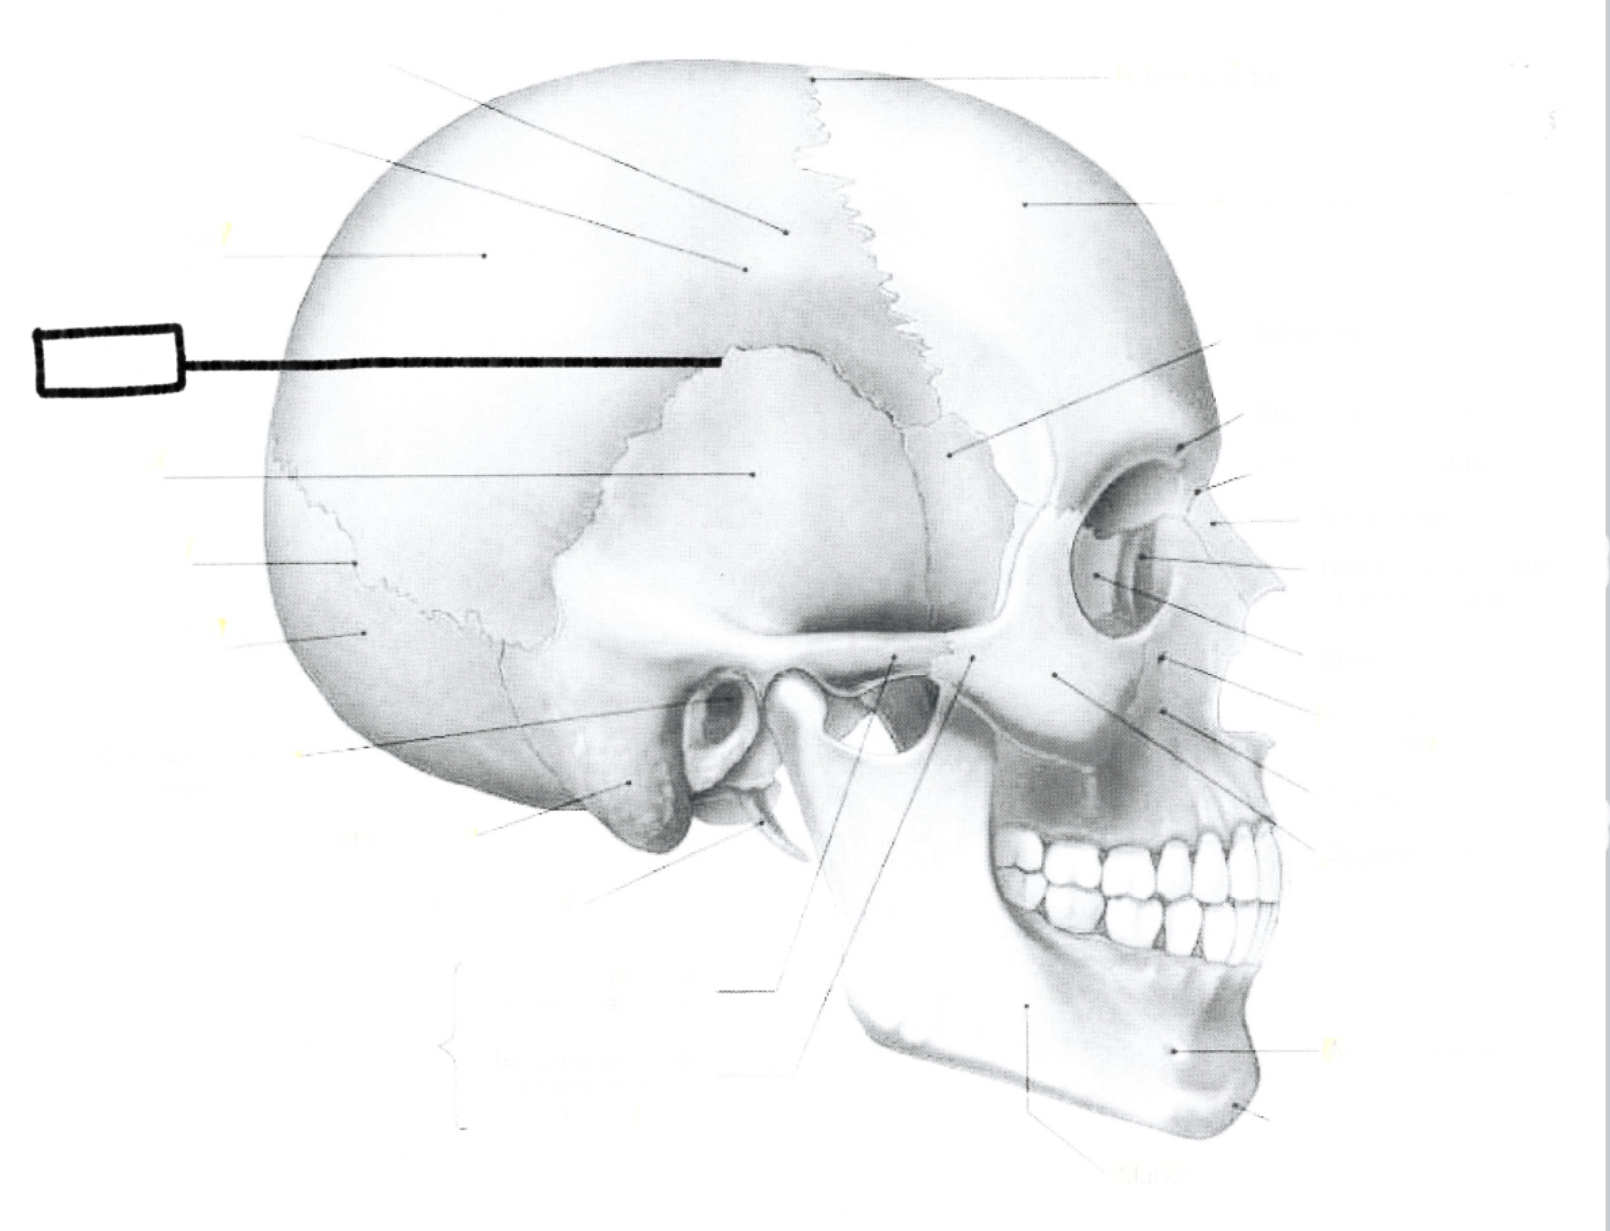

What is this?

Parietal bone